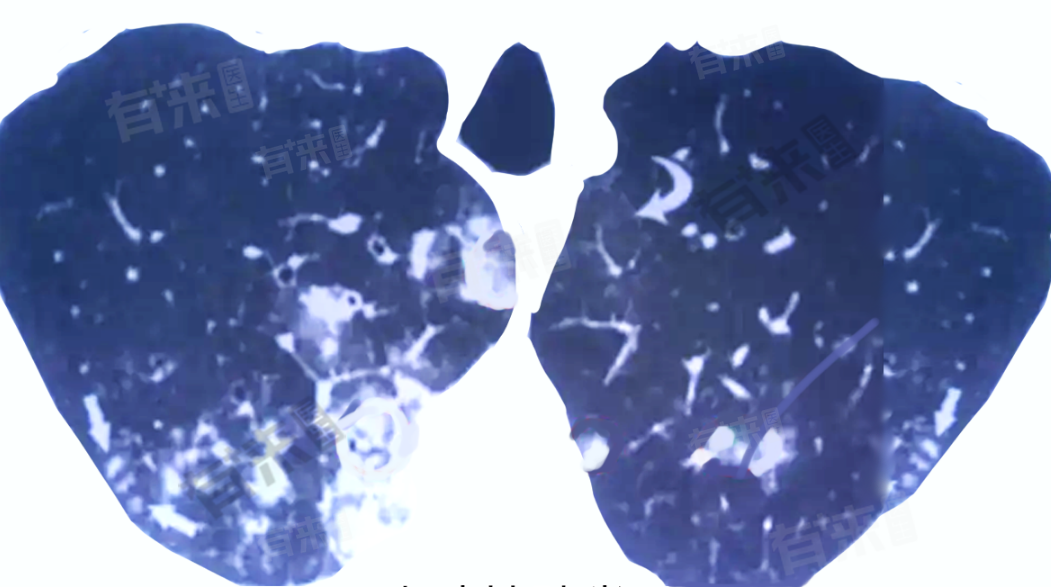

肺叶钙化灶是指在肺部的X射线或CT扫描中,可见的小结节或病变区域显示出高密度的钙沉积,通常与多种原因有关,包括病后愈合、恶性疾病等。

- 大多数肺叶钙化灶是良性的,代表肺部曾经的病变过程已经愈合,对身体通常没有不良影响,无需特殊治疗,只需定期复查,观察钙化灶的变化即可。

- 虽然恶性原因引起的肺叶钙化灶较为罕见,但如果钙化灶周围出现毛刺、分叶或阴影继续增大等异常变化,应警惕恶性病变的可能性,需进一步行肺穿刺、支气管镜等检查以明确诊断。